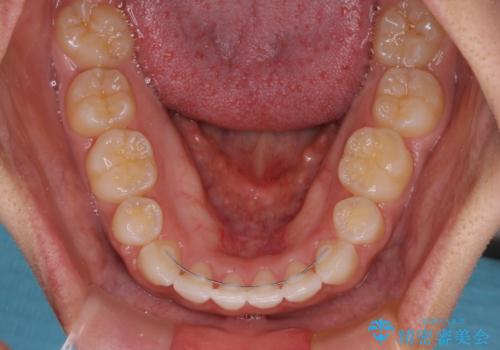

- メタルブラケット

- 3年1ヶ月

上下前歯部の被蓋関係を改善するの時間がかかり、3年間を要することとなりましたが、スッキリとした口元に仕上がりました。